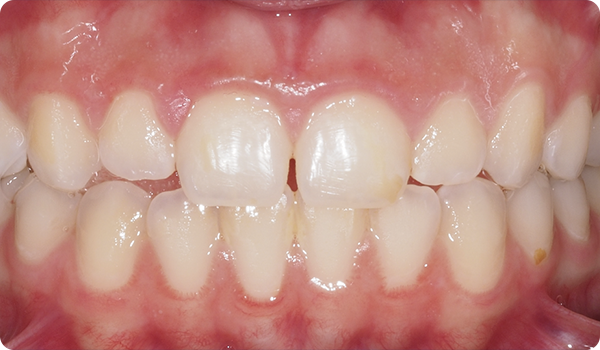

Designet til protetikere. Med små bevægelser korrigeres malpositioner og forbereder den mest egnede og konservative æstetiske behandling for dine patienter.

Enkle behandlinger: små bevægelser op til 1 mm og 15º rotation.

Enkle behandlinger: små bevægelser op til 2 mm og 30º rotation.

Mildere behandlinger: små bevægelser op til 3 mm og 40º rotation.

Mildere behandlinger: små bevægelser op til 3 mm og 50º rotation.